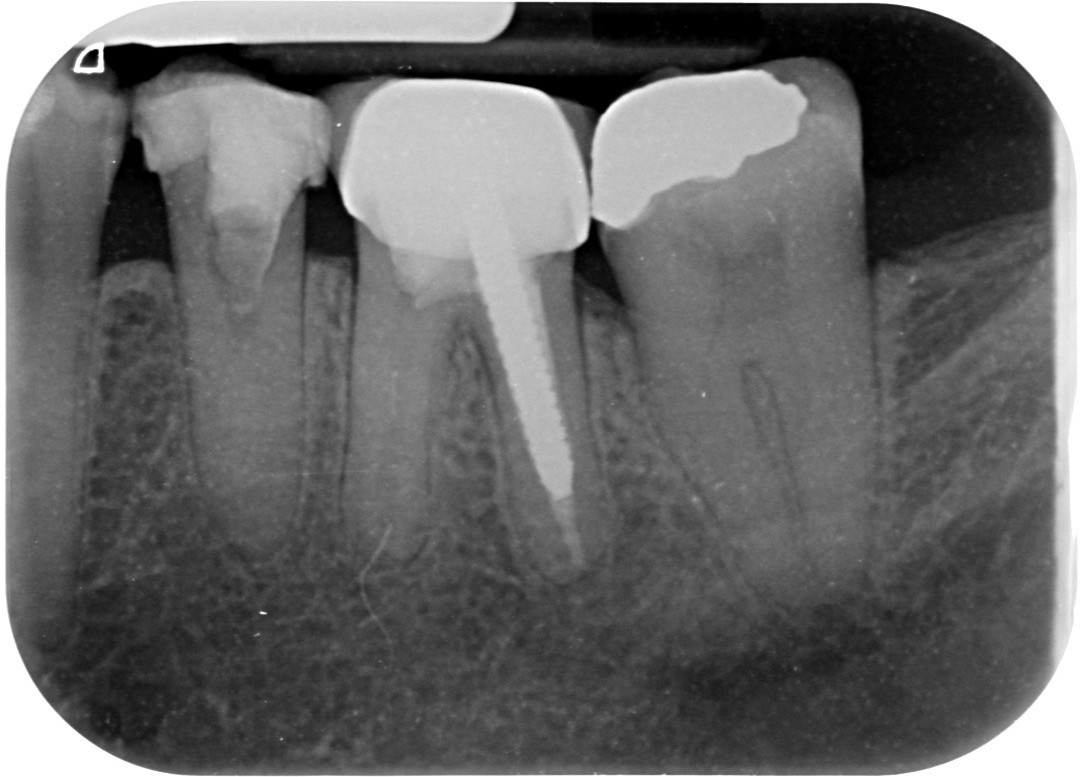

4. What option can describe the post placement in the X ray bellow for the tooth # 3.6?